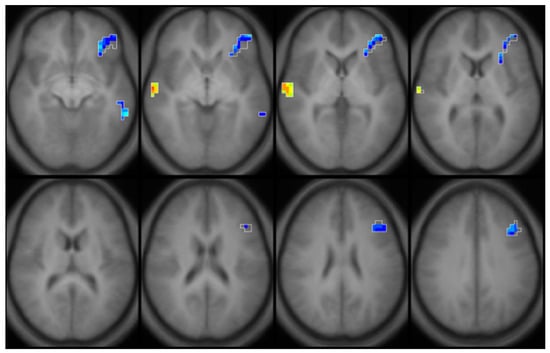

- de Water, E.; Papazaharias, D.M.; Ambrosi, C.; Mascaro, L.; Iannilli, E.; Gasparotti, R.; Lucchini, R.G.; Austin, C.; Arora, M.; Tang, C.Y.; et al. Early-life dentine manganese concentrations and intrinsic functional brain connectivity in adolescents: A pilot study. PLoS ONE 2019, 14, e0220790. [Google Scholar] [CrossRef] [Green Version]

- de Water, E.; Curtin, P.; Zilverstand, A.; Sjodin, A.; Bonilla, A.; Herbstman, J.B.; Ramirez, J.; Margolis, A.E.; Bansal, R.; Whyatt, R.M.; et al. A preliminary study on prenatal polybrominated diphenyl ether serum concentrations and intrinsic functional network organization and executive functioning in childhood. J. Child. Psychol. Psychiatry 2019, 60, 1010–1020. [Google Scholar] [CrossRef] [PubMed]